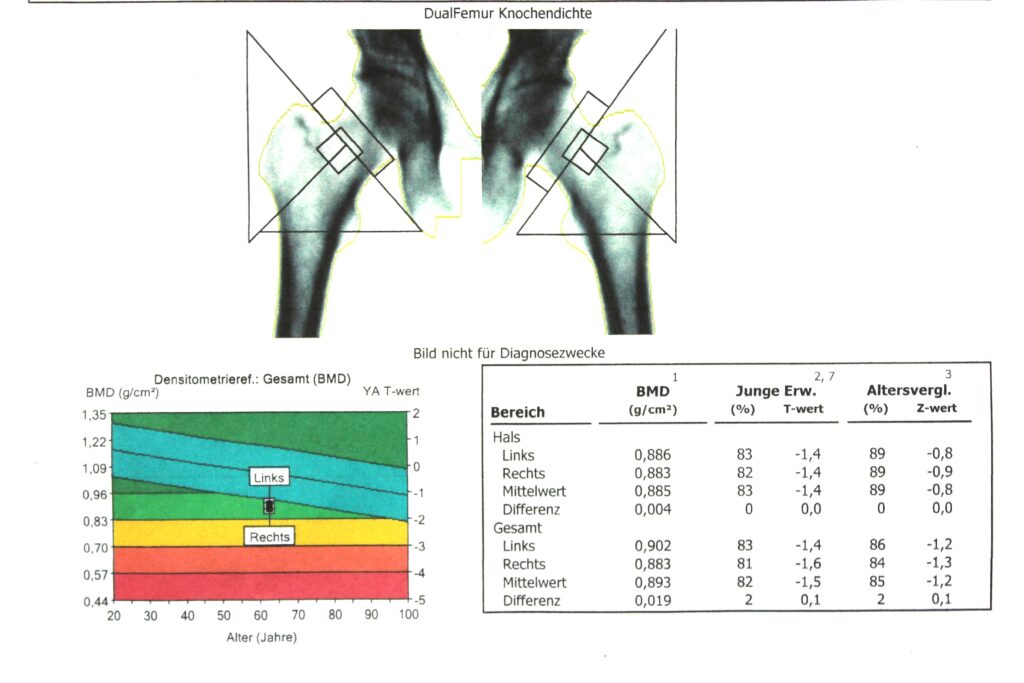

Knochendichtemessung (DEXA)

Die DEXA-Messmethode wurde weltweit zum „Goldstandard“ erklärt. Hiermit ist es möglich die erhaltenen Messwerte (T-Werte) leitliniengerecht (DVO) in das Therapieschema einzuordnen.